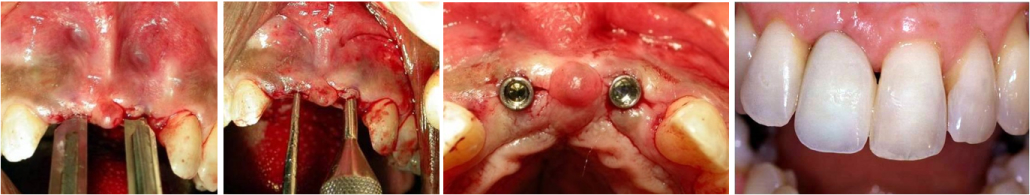

1mm ridge expanded by bone renaissance to receive a 4.5 mm implant followed by ideal restorations

The atraumatic, innovative, essentially a flapless surgical technique is designed to expand an initial osteotomy created by inserting the scalpel blade first by pushing and then by careful malleting to bisect attached gingiva and ridge. The socket development begins with the use of the blade #15 to separate the labial and the lingual plates. Blade is tapped between the buccal and lingual walls followed by the instrument #2 which is slightly more wider than the blade. Specially developed and designed bone osteotomes are used to expand narrow ridges to improve the density and complete molding of the bone against the sides of the implant site.

In extremely dense and atrophic mandibular ridges, the socket development begins with the use of the blade #15 to separate the labial and the lingual plates, followed by the instrument #2 open the crestal window to introduce the sharp pointed pilot drill of 1.5mm diameter at a speed of 1500-2000 rpm with profused irrigation to a depth of 8 mm to 10 mm, creating an osteotomy of 1.5 mm in diameter.

As instruments are introduced into the bone, cortical and cancellous bone is enthused outwards compacting it against the face of implant socket. Use 1.5mm in diameter straight manual osteotome for anteriors and offset for posteriors. Gently push and tap into the initial site, followed by 2mm wider until you reach the desired depth. Next connect the motor driven osteotome # 1 in the hand piece with a speed of no more than 50 rpm & torque between 15-25 N followed by # 2 & 3. The specific drill and bone expander sequence may vary according to the bone quality and quantity and the desired diameter of the implant. Drilling bone to prepare implant sites is only required in situations where extremely dense bone is encountered. In such situations widen the opening so that a drill may be inserted easily without touching the crestal bone. If this crestal bone is too thin less than 0.75 or so then do some augmentation by adding and burnishing particulate graft. If a resistance is encountered due to the cortical bone just take a 2mm diameter drill and gently shave off the bone beside the hole. If the bone is relatively soft (as in maxilla) don’t use the drills it would be more desirable to use a combination of hand or motor driven osteotomes according to convenience and approach. Expansion should be switched to a hand ratchet and the instruments may be inserted at intervals, slow motion pausing for a while to allow time for blood circulation and the bone to expand, introducing progressively larger osteotomes, as needed and repeating the rotating and manual strokes.

Continually enlarge the opening by utilizing a combination of motor-driven & mallet-driven bone expanders together with an amalgamation of autologous growth factors in a sequential, codified approach to achieve an unsurpassed implant stability. The density of the bone adjoining the implant in so doing is tremendously improved and augmented. Osteoplasty is achieved by using a series of blunt osteotomes which are repeatedly moved forwards & backwards to amalgamate and burnish the particulate bone in the osteotomy together with concentrated growth factors collected from the patient’s autologous blood and this simultaneously augment and enlarge the osteotomy up to the desirable width. With this, the bone layer next to the osteotomy is improved because of the compaction of bone which in turn helps anchor a desirable endosseous implant.

Stages of bone renaissance manipulation

Immediate Implant Socket Development: In cases of Immediate implants in multi-rooted teeth, the most desirable socket is selected and the bone manipulation is initiated at a more palatal position, and then mechanically oriented in the desired direction by applying pressure on the bone expanders/ osteotomes as it manipulates, rotates while advancing into the atrophic ridge along with the repositioning, directing, gently pushing, molding manually and mechanically together with the addition of particulate graft. The expanders are driven at speeds between 20 rpm – 50 rpm with torque about 15-25 Ncm. Rotary expanders may additionally be used to pack the grafting material. Although the narrower bone expanders may be utilized to penetrate the sinus floor, caution must be taken because of the increased risk of perforating the Schneiderian membrane. Blunt apical design, expanders are designed for this purpose. Use of Bone Renaissance concept to expand an osteotomy by burnishing helps to maintain all of the existing bone material by pushing the bone aside with minimal trauma while developing an accurately shaped osteotomy. Smooth-sided osteotomes are used to burnish the graft and further condense the bone, while the threaded design of the motor-driven bone expanders prepares taps in the osteotomy site where there is extremely dense bone that further facilitate the subsequent insertion of a threaded implant, and greatly enhances the initial stability as well.